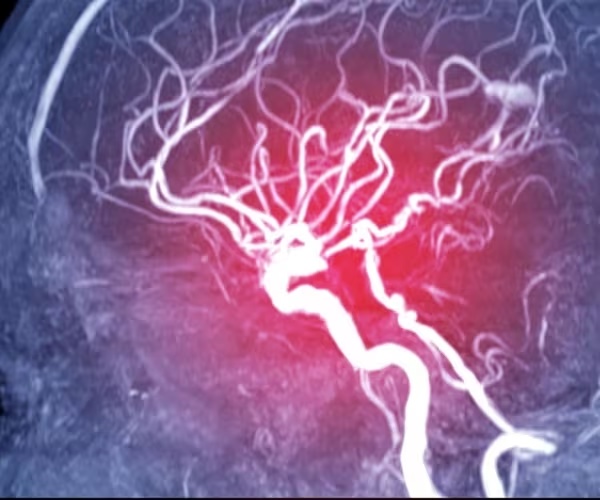

Lab-grown blood vessels are providing new insight into how damage to the tiny vessels in the brain can cause them to leak, contributing to dementia and stroke.

Cerebral small vessel disease (SVD) contributes to almost half (45%) of dementia cases worldwide, researchers said in background notes.

It is also responsible for about one in five (20%) ischemic strokes, which occur when a blood clot blocks blood flow to the brain. Most cases are associated with chronic illnesses like high blood pressure and type 2 diabetes, and they typically affect people in middle age.

Blood vessels are built around a scaffolding called an extracellular matrix, which lines and supports the tiny vessels in the brain. The COL4 gene is important for the health of this matrix.

Researchers found that disruption of this matrix leads to small blood vessels becoming leaky.